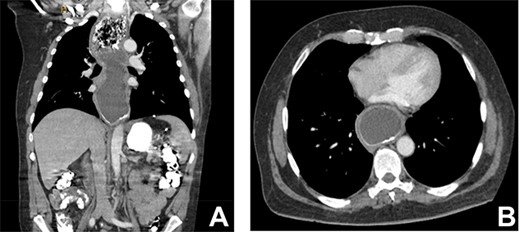

As part of the assessment, computed tomography (CT) coronary angiogram study was performed and it demonstrated a large fluid-filled oesophagus causing partial compression of the left atrium. Barium swallow (Fig. 1A and B), CT chest and abdomen (Fig. 2A and B) and transthoracic echocardiography (TTE) showed a 7.1-cm dilated oesophagus causing left atrial compression and a small hiatal hernia (Fig. 3).

(A) CT coronal image of chest and abdomen demonstrating megaoesophagus secondary to the LAGB; (B) CT axial image of chest demonstrating megaoesophagus causing left atrial compression.

In the case of this patient, the extent of his megaesophagus resulted in significant compression of the left atrium observed on TTE and CT, which fortunately did not cause haemodynamic compromise or obvious and clinically evident intracardiac thrombus. To our knowledge, compression of the cardiac chambers by oesophageal dilatation is an extremely rare complication of LAGB. A systematic literature review of megaoesophagus in LAGB patients was performed (Table 1).